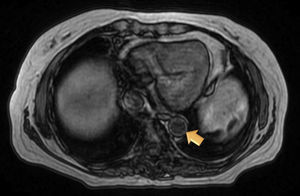

Magnetic resonance (MR) angiography of thoracic aorta and the upper portion of abdominal aorta (Fig. 1) showed a somewhat thickened aortic wall, reaching a thickness of approximately 1.7mm in prerenal aorta, with atheromatosis in thoracoabdominal aorta (thoracic CT disclosed significant calcification in thoracoabdominal aortic wall). These 2 examinations indicated a possible diagnosis of arteritis, predominantly aortitis, and constitutional symptoms in a patient with SLE. To rule out other associated processes, the patient underwent positron emission tomography (PET)/CT with 18F-fluorodeoxyglucose (FDG) (Figs. 2 and 3), which showed abnormal FDG uptake along the wall of thoracic and abdominal artery. The aortic arch, descending thoracic aorta and pulmonary artery were found to be involved. In abdomen, there was an increase in FDG uptake along the entire length of the abdominal aorta, which affected superior mesenteric artery (SMA) and extended to the common iliac bifurcation. It was associated with foci of calcified atheromatosis.